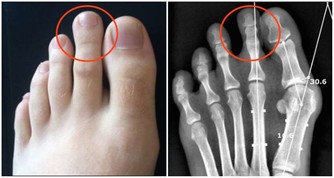

此研究綜合9個全球性臨床試驗,共1069名受試者,包括美國、比利時、日本等國家,比較37個項目,結果發現,解熱鎮痛藥雖然可以改善頭痛、耳朵痛、肌肉與關節疼痛等現象,卻無法改善咳嗽、流鼻水等呼吸道症狀。